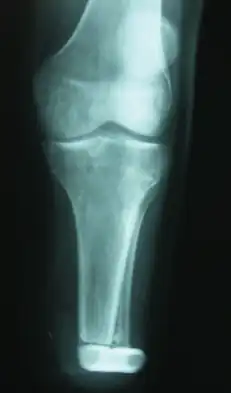

W zdjęciu rentgenowskim (RTG) może być widoczny okrągły lub owalny guz z obecnymi płacikami, czasem bywają widoczne zwapnienia w masie guza[34]. W 15–20% przypadków pojawiają się cechy inwazji kości z obecnością odczynu okostnowego, erozji lub nacieczenia kości[33][34]. Intensywna inwazja kości jest rzadka, zwykle dotyczy podtypu niskozróżnicowanego albo długiej obecności guzów o dużej masie. Na radiogramach bywa obserwowalne samoistne kontrastowanie się guza związane z obecnością drobnych zwapnień, co może sprawiać pewne trudności z różnicowaniem z pozaszkieletowym kostniakomięsakiem[34].